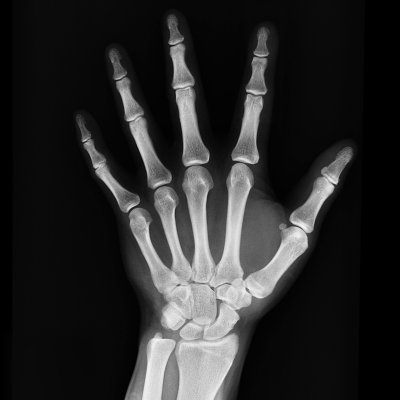

X-rays can help show these changes clearly. Healthy joints have an even, open space with no bone growths. In more advanced cases, the joint space narrows, and bone spurs may appear, often leading to reduced flexibility and discomfort.